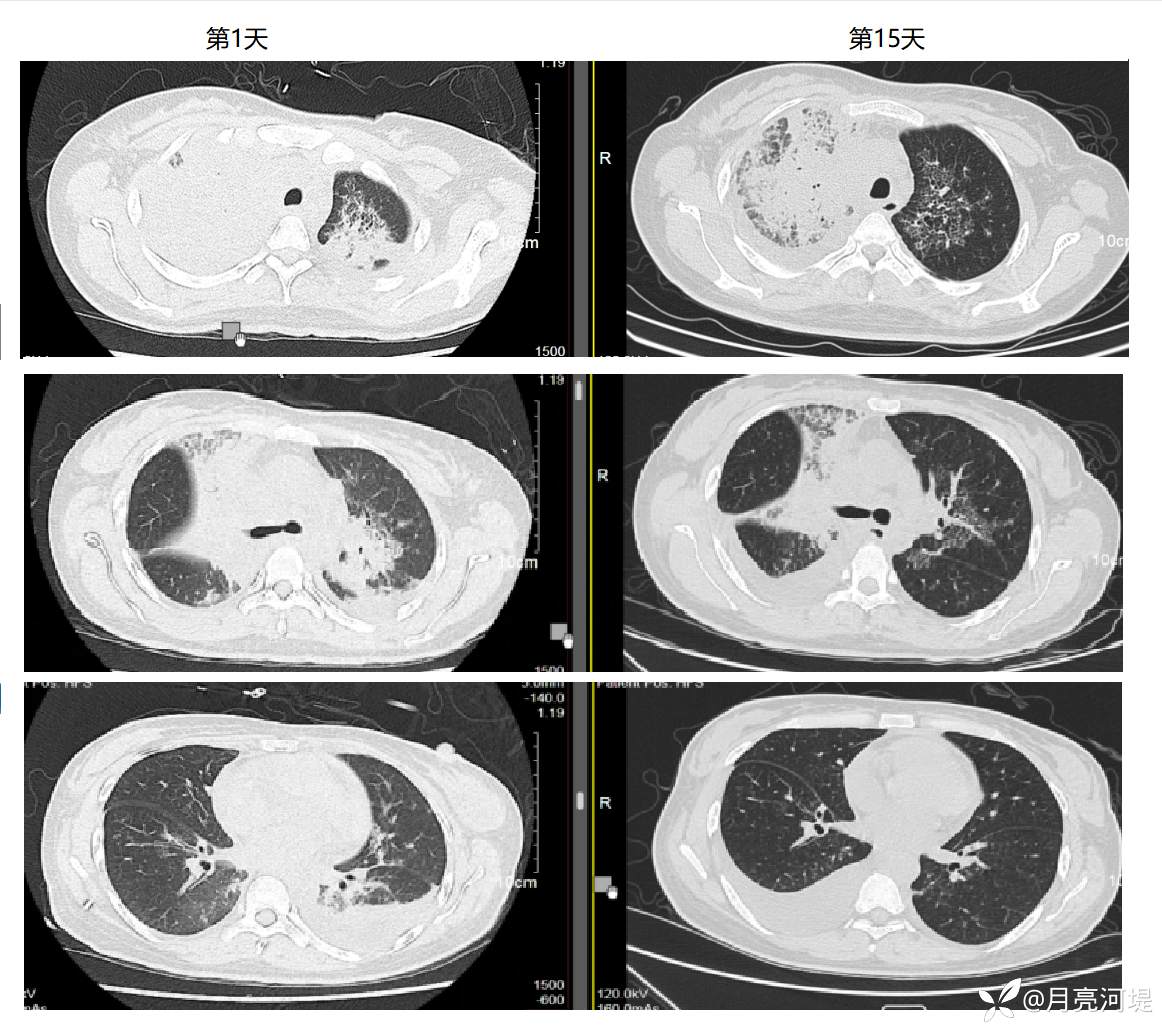

胸部CT示两肺间质性炎症、局部多发细小蜂窝,右肺上叶大片状实变,右侧胸腔积液伴右肺下叶部分膨胀不全。PET-CT提示纵膈多发淋巴结明显肿大伴高摄取,但2次穿刺活检未提示肿瘤或肉芽肿。

【治疗经过及结果】:先后哌拉西林、万古霉素、泰能等治疗均无效,每天39℃以上高热,甲强龙40mg/d静滴控制体温数日,但后又出现高热,因无结缔组织病依据停用激素。高热时予地塞米松静推或泰诺林口服可退热,热退后精神好,轻度咳嗽,痰不多,无明显胸闷气促,心率呼吸氧和均稳定。抗感染2周后复查肺部CT实变病灶略有好转,期间CRP波动于50-90mg/L,IL-6 波动于50-300pg/mL,PCT波动于 0.20-0.38ng/ml。